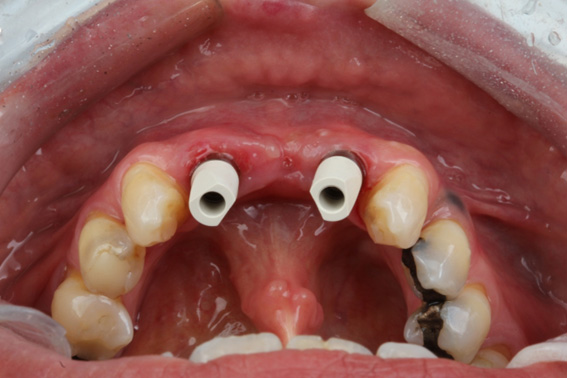

3 | Alveoli immediately after tooth extraction. Occlusal view